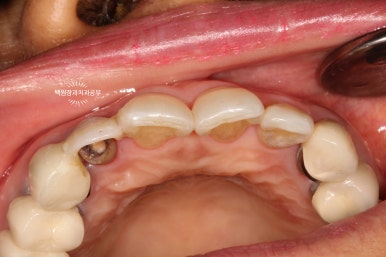

치아를 약간 정출시킨 후 봉합사를 이용하여 고정해줍니다.

보시는 바와 같이 치아를 약간 정출시켜줍니다. 대개는 2-3mm 정도 정출시킵니다.

오른쪽 사진을 보시면, 입천장 쪽에서 보았을 때 치아가 보다 더 정출한 것을 보실 수 있어요.